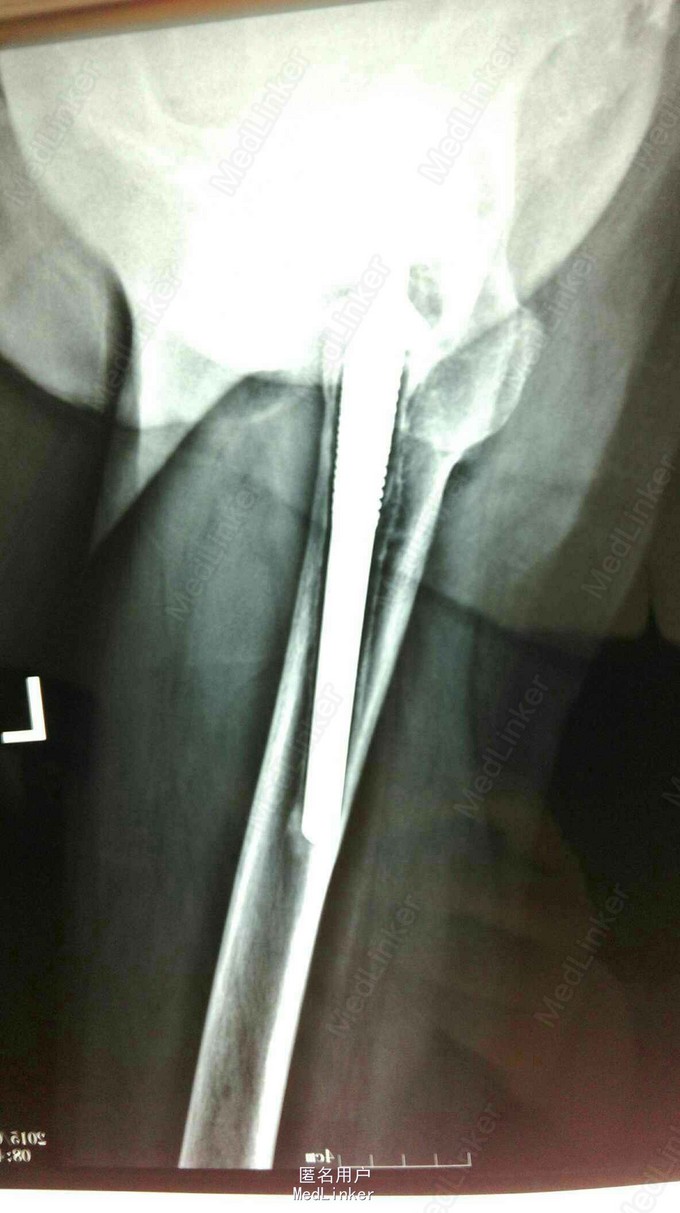

髋关节置换术后15年,疼痛2年。 15年前左股骨头坏死,在外院行股骨头置换术,2年前左下肢短缩,左髋关节疼痛,活动受限。

左股骨头置换术后假体松动 完善术前检测后行髋关节翻修术,术中髋臼侧打压植骨,术后左下肢短缩1cm ,顺利出院。